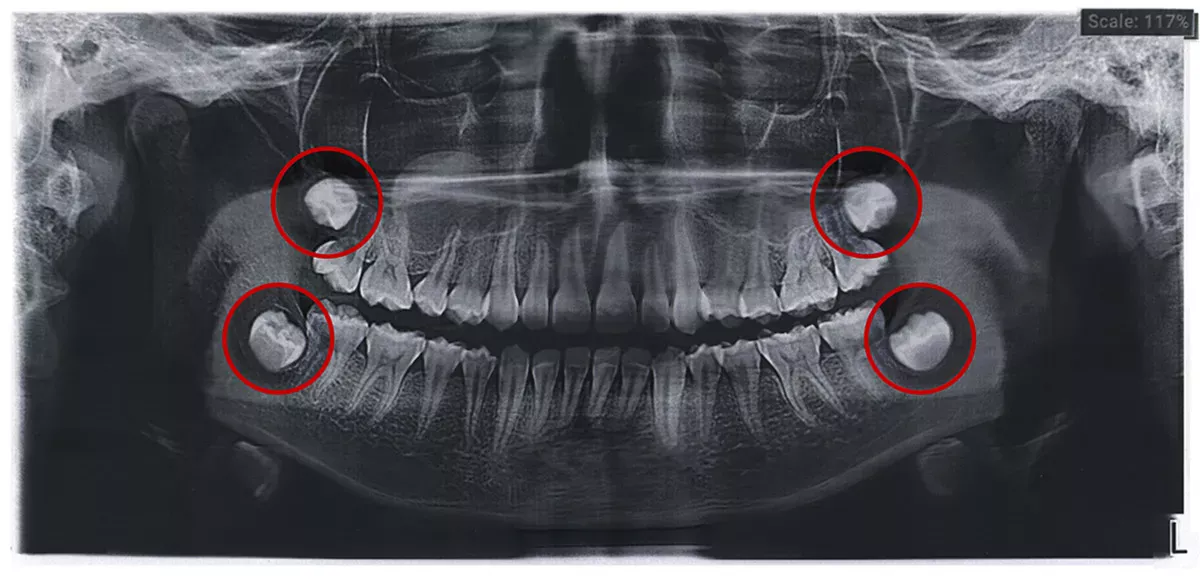

In this article you will find some pictures of wisdom teeth - both x-rays and photos of extracted teeth and graphics - to give you a good idea of what wisdom teeth look like.

Cysts can also form on impacted wisdom teeth, which the dentist can recognise on an X-ray. Cysts are filled with fluid and do not initially cause any pain. However, if they become inflamed, they can cause a feeling of pressure and dull pain.

If you keep your wisdom teeth in your mouth and do not have them extracted, you have the advantage of being able to use them for a tooth transplant for a damaged or missing tooth instead of having to insert an implant. You and your dentist will decide whether your wisdom teeth should be extracted or not based on the x-rays.